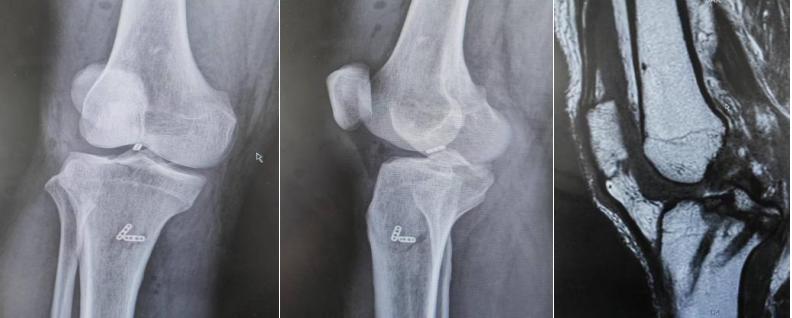

术后x线及磁共振

吕荼团队经过认真讨论和周密准备,采用三button技术固定复杂胫骨后叉撕脱骨折,并同期修补外侧半月板。术后影像显示患者骨折复位良好,解剖复位,术后胫骨后沉消失,抽屉试验(-),半月板位置、形态良好。